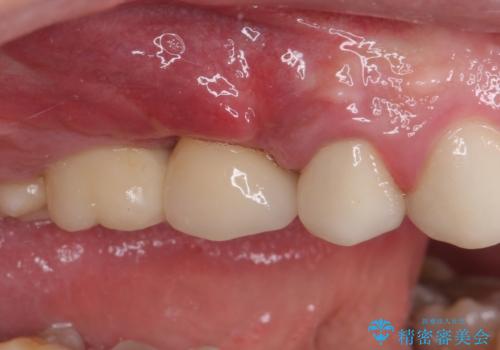

折れてしまった歯 インプラントによる補綴治療

- 咬合力により歯が割れてしまった方のインプラント治療です。

抜歯後4ヶ月ほど待ち、後方のインプラントと同一メーカーのインプラントを埋入することとしました。

大変怖がりであるため、インプラント治療の際には静脈内鎮静により、眠っている間に手術を行いました。

別途費用はかかりますが、術中の記憶はほとんどなく、処置もあっという間に終わった感覚となるので、大変お勧めです。